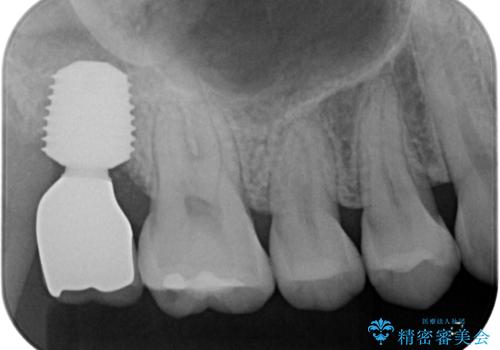

右上のインプラント治療は、1DAYインプラント治療(抜歯即時埋入・即時荷重)の適応となりましたので、通常3回必要な外科処置の回数を1回に集約させることができました。

口腔内の環境が大きく改善し、現在はご自身のプラークコントロールにより良い状態が維持できるようになりました。